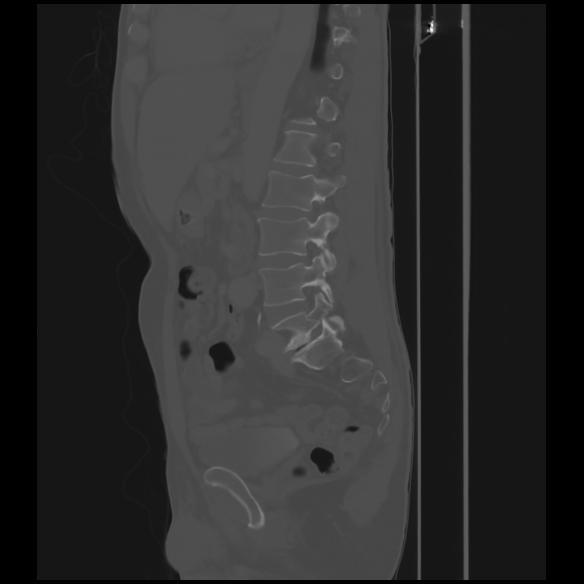

7 CUERPO,CE,Sagittal,3.000,CUERPO,Sagittal,